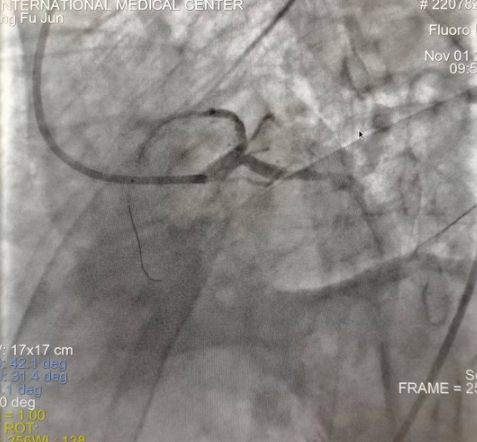

閉塞的血管再通時間取決于急救時長、轉(zhuǎn)運時長和治療時長,在前兩方面,醫(yī)院已為患者爭取了最短時間?;颊呒覍龠h在陜北,雖然已在趕來的路上,但最快抵達西安也要3小時,在與患者家屬電話溝通同意急診手術(shù)后,醫(yī)療總值班代家屬簽字,康曉軍在請示心臟病醫(yī)院王海昌院長及心臟內(nèi)科CCU尚福軍主任后,積極進行術(shù)前準備。在沒有家屬陪同、沒有交費、沒有辦入院手續(xù)的情況下,患者經(jīng)胸痛中心綠色通道被送往心臟冠脈介入手術(shù)室,打通了完全閉塞的心臟前降支近段血管。